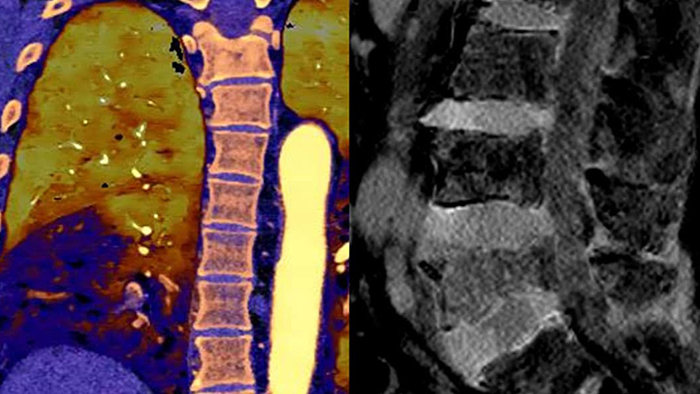

Unlike traditional CT images, spectral-detector CT images capture spectral information 100% of the time —without special planning or set-up. That means you can analyze the spectral data in any image retrospectively, using a variety of spectral viewing tools. You can, for example, adjust the monoenergetic level or get Zeffective maps.

Spectral detector simultaneously absorbs and differentiates high and low energy from a single polyenergetic X-ray beam. Spectral results are acquired within a single scan without the need for special modes.

Detector-based spectral CT simultaneously absorbs high and low energies in the same time and space.